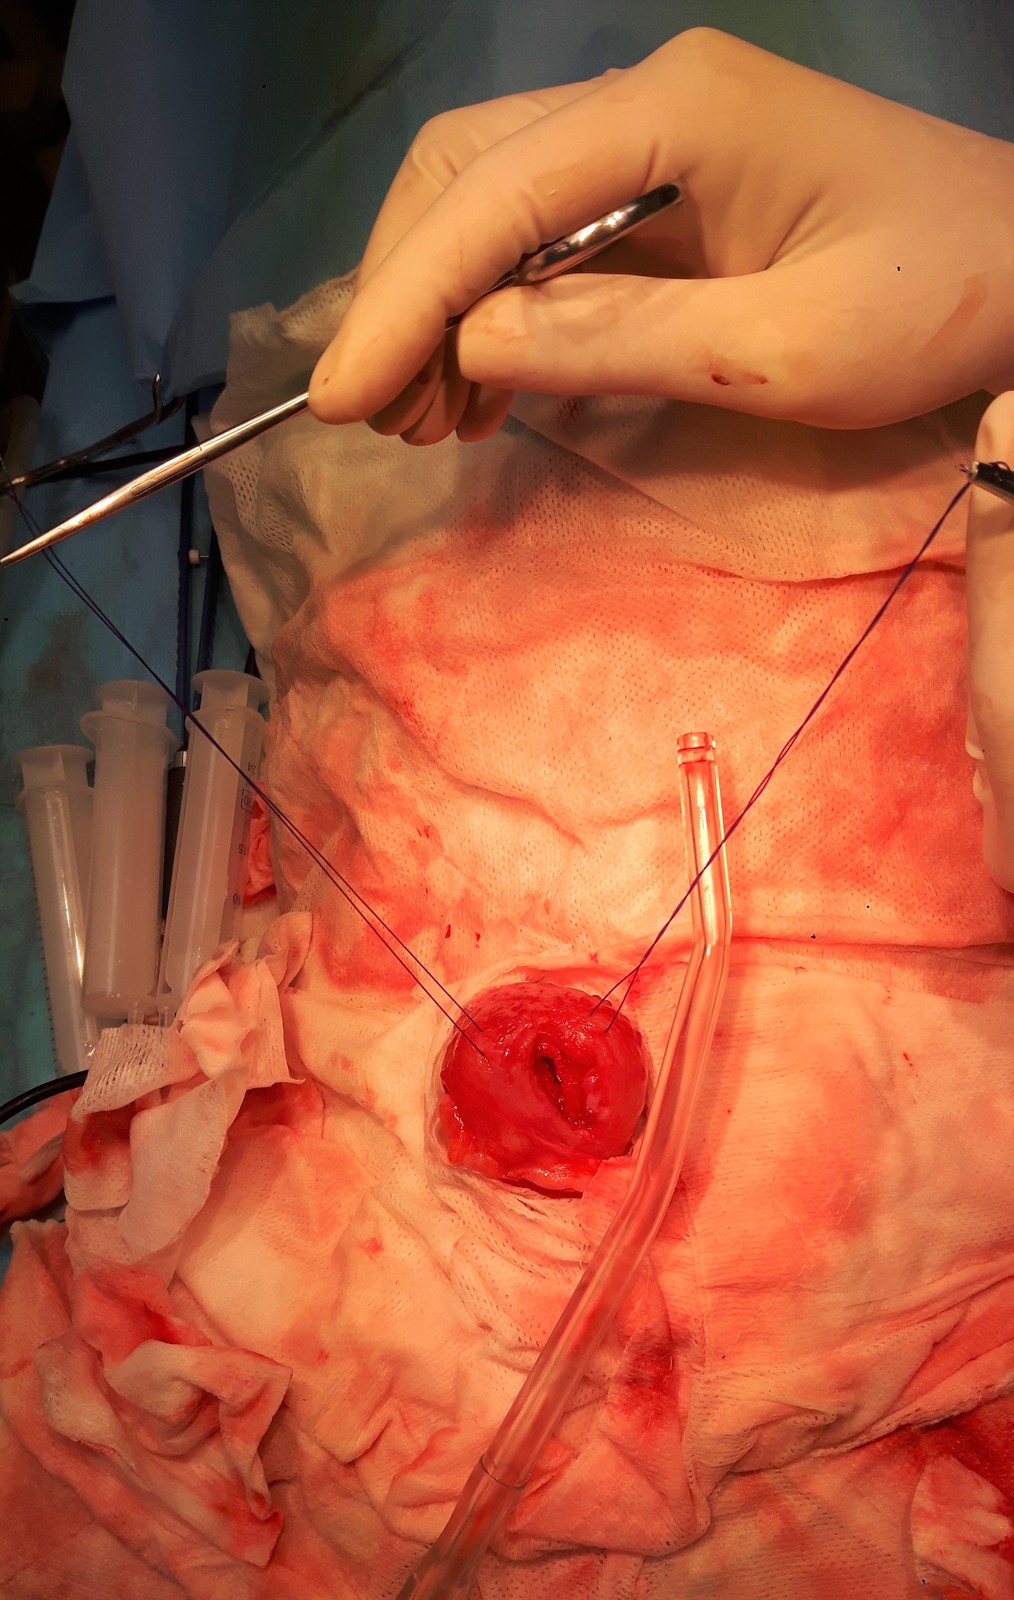

Před operací jsme Agáthě provedli cystocentézu močového měchýře pod USG kontrolou a následně zavedli do močového měchýře sterilní močový katetr, prodloužený o sterilní prodlužovací hadičku, určený k peroperačním výplachům močového měchýře a uretry.

FOTO před operací 1.jpg

Agáthu jsme připravili na otevření dutiny břišní.

Po otevření dutiny břišní jsme odrouškovali močový měchýř, který byl palpačně zcela vyplněný drobnými urolity.